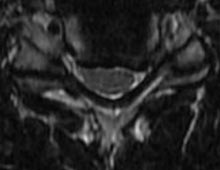

50 year old man presenting with left biceps and triceps weakness with numbness in his hand.

C6 corpectomy with complete resolution of the weakness and numbness.